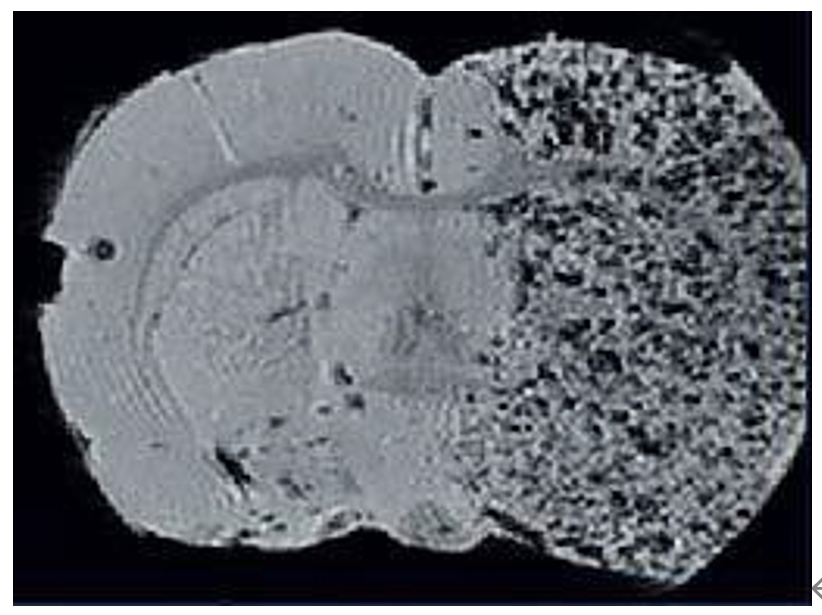

磁共振成像低溫探頭增加150%的靈敏度,清晰顯示小鼠腦部細(xì)胞層狀結(jié)構(gòu)(小腦的顆粒層和浦肯雅細(xì)胞層),空間分辨率達(dá)到 50μm:

利用標(biāo)記Fe的間質(zhì)干細(xì)胞來顯示大鼠中風(fēng)區(qū)域: